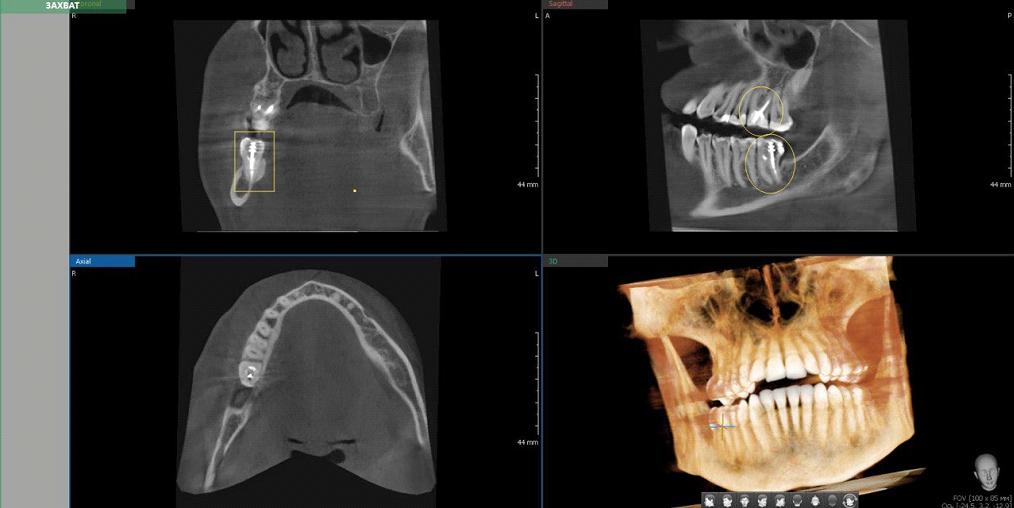

В овалах штифтовые конструкции. В прямоугольнике видна горизонтальная исчерченность — это помехи от металла штифта.

Если мы видим такие помехи, то делаем единичный прицельный снимок, где отражение уже не мешает:

Тот же зуб из примера выше на прицельном снимке